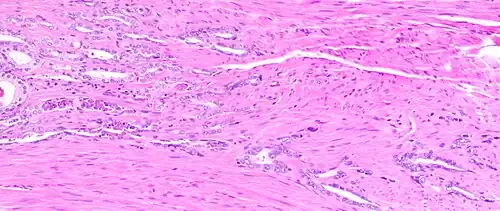

Histology of normal prostate, H&E stain, with benign features: Glands are rounded to irregularly branching, with an inner layer of epithelial cells surrounded by an outer layer of basal cells. They are surrounded by ample stroma. -